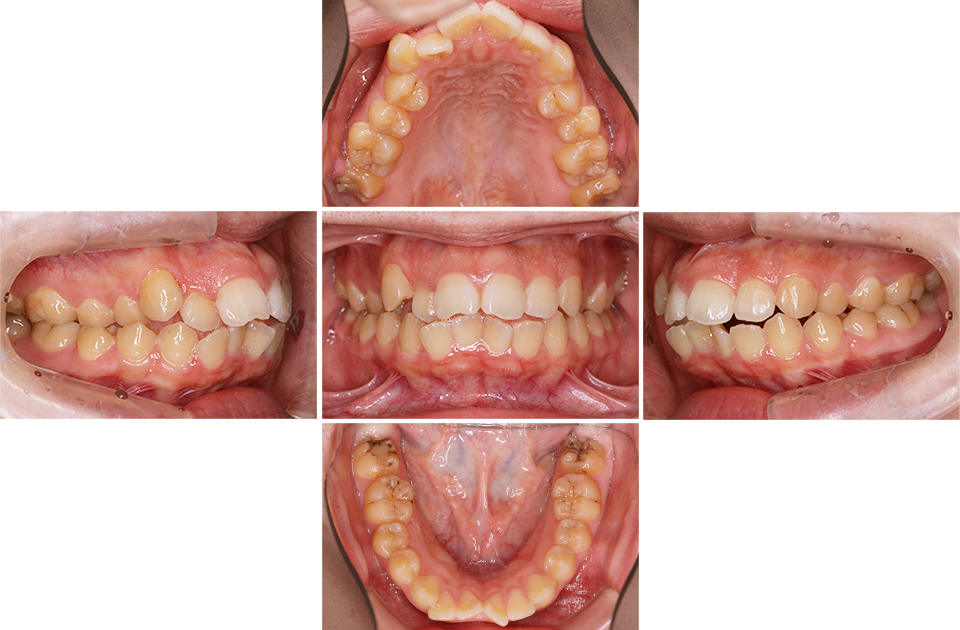

矯正前

矯正前 正面

矯正前 右側

矯正前 左側

矯正前 上顎

矯正前 下顎